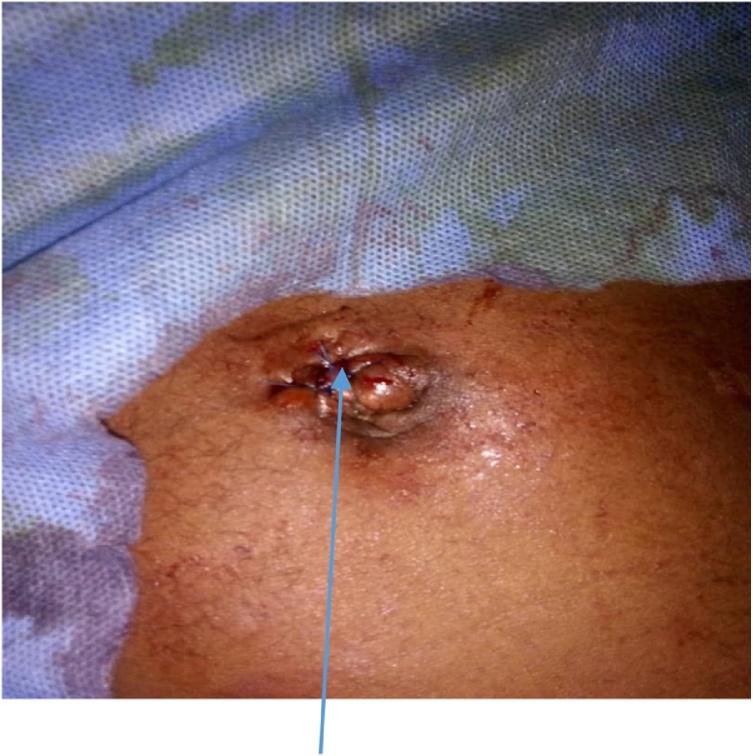

A two-port technique was used to retrieve the pin. These ports consisted of optical supra-umbilical port (10 mm) and left iliac fossa port of 10 mm. They were aligned in the direction of sharp end of the foreign body, to aid retrieval of the Steinmann pin. This procedure was performed on a 34-year-old man who presented with migration of Steinmann pin into abdominal cavity. He had open reduction of old unreduced left posterior hip dislocation. A Steinmann pin with a diameter of 4.5 mm and length of 140 mm was passed through the greater trochanter to the acetabular roof. The protruding end of the pin ought to have been bent. Three weeks post-surgery, the pin migrated. Physical examination revealed vague tenderness over supra pubic region. A hard pointed object was palpable in the right iliac fossa. Abdominal X-ray and ultrasound were suggestive but not definite for pin location.

采用双孔技术取出斯氏针。这两个孔包括脐上光学孔(10毫米)和左髂窝10毫米孔。它们与异物尖锐端的方向对齐,以协助取出斯氏针。该手术在一名34岁男性患者身上进行,该患者的斯氏针迁移至腹腔。他曾接受陈旧性左后髋关节脱位切开复位术。一根直径4.5毫米、长度140毫米的斯氏针穿过大转子至髋臼顶。针的突出端本应弯曲。术后三周,针发生迁移。体格检查发现耻骨上区域有模糊压痛。在右髂窝可触及一个硬的尖状物。腹部X线和超声检查对针的位置有提示作用但不明确。